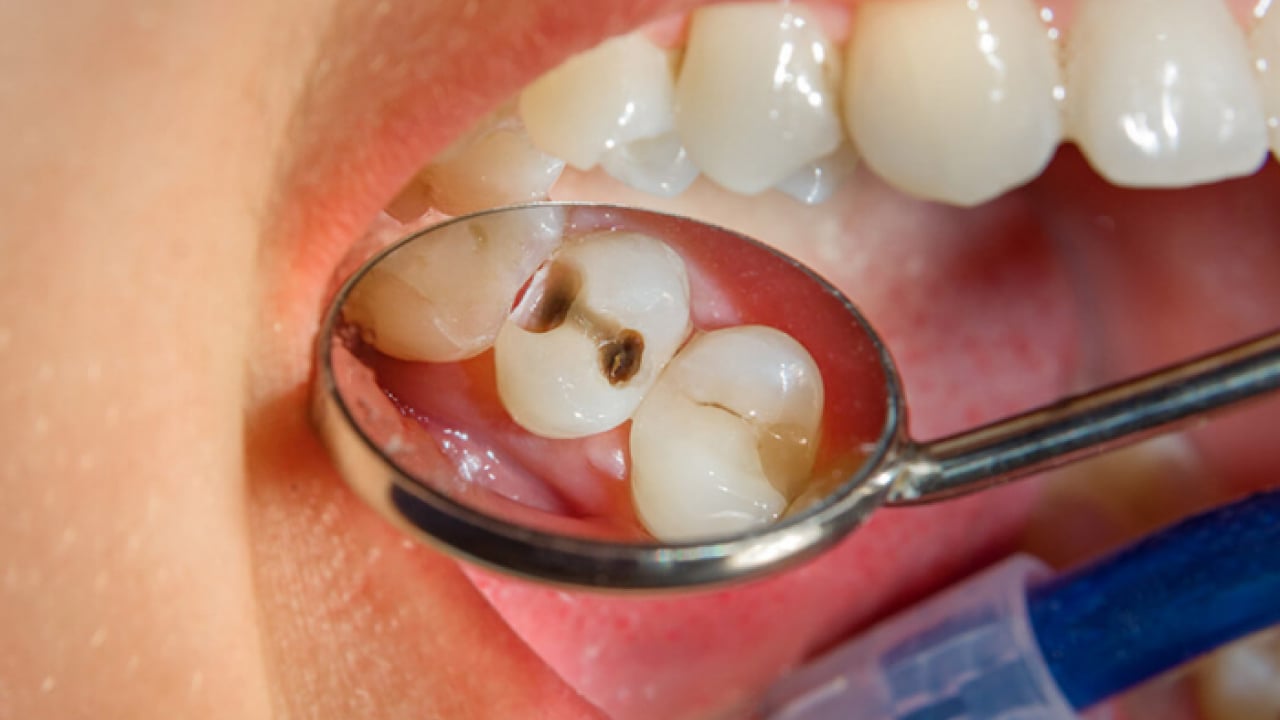

Dr. Öğr. Üyesi Sezer, "Dişin kök kanallarındaki sinir ve damar dokusu temizlenir, kanal duvarları arındırılır ve uygun materyallerle doldurularak diş restore edilir. Geçmeyen zonklayıcı ağrılar, gece uykudan uyandıran şiddetli ağrı, yüzde şişlik oluşturan apse, yemek yerken sıcakla veya dişe bastırınca oluşan hassasiyet gibi durumlar kanal tedavisi gerekliliğini düşündürür" diye konuştu.

“TEDAVİ YAPILMAZSA DOKU HASARINA YOL AÇABİLİR” Kanal tedavisi yapılmazsa dişte veya vücutta hangi sorunlar görülebileceğine değinen Dr. Öğr. Üyesi Sezer, "Kanal tedavisi yapılmadığında kök ucunda oluşan lezyonlar büyüyerek kistleşebilir, büyük kemik kayıplarına ve doku hasarına yol açabilir. Dişte sürekli hassasiyet ve spontan ağrılar oluşabilir. Kronikleşmiş enfeksiyonlar bazen akut şekilde ani yüz şişliklerine dönüşebilir yahut ağrı vermese bile zaman içinde ilerleyebilir. Ağız içindeki bu enfeksiyon odakları diyabet, kalp hastalıkları gibi sistemik durumları kötü etkileyebilir. Dişlerin tedavi edilmeyip durumları kötüleştiğinde çekilmek zorunda kalınması, çiğneme fonksiyonunda bozulmaları ve bununla beraber bağışıklık sisteminin zayıflamasını da beraberinde getirir" dedi.